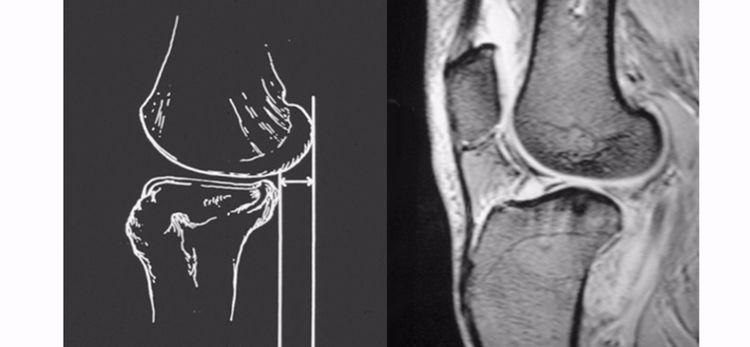

要提高ACL损伤MRI诊断的准确性,解剖永远是基础!同时,还需要充分了解ACL的受伤机制,针对性的阅片;MRI的矢状位、冠状位及轴位三者结合,以提高诊断的准确性与全面性!

ACL的正常MRI表现——

1.各序列均为低信号。

2.韧带平直,边界清楚,有较好的张力。

3.韧带内可有脂肪及滑膜条纹影。